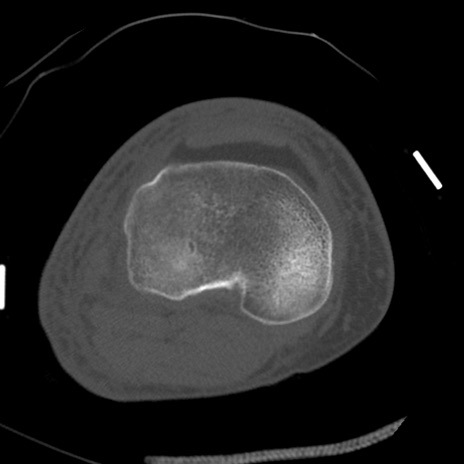

症例28 右膝関節CT(横断像)

右膝関節CT